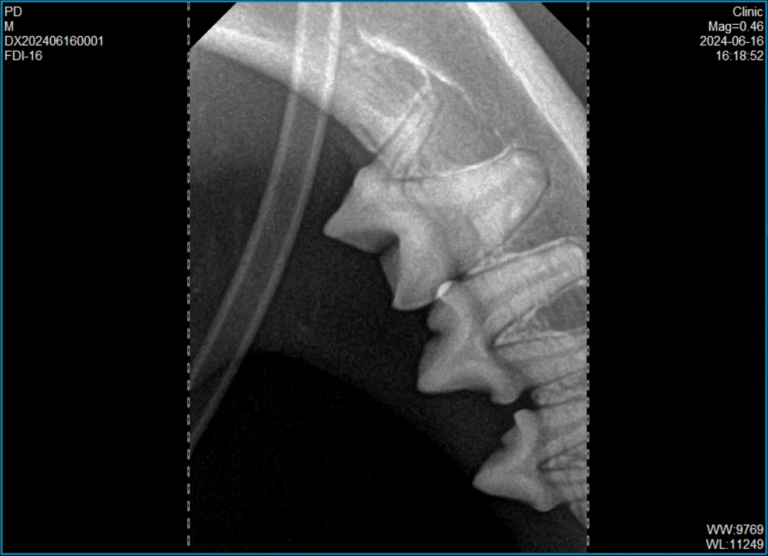

Vet Dental